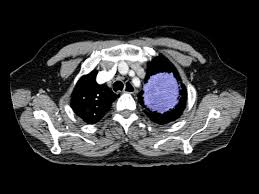

Chemotherapy is useful in treating types of cancer that affect the whole body, including lymphoma. Primary lung tumors and metastatic lung tumors. Those that do may have difficulty breathing (labored or rapid breathing, even while resting), reduced ability to manage walks (exercise intolerance), decreased appetite, weight loss, coughing or sneezing (with or without discharge. Feline cancer initially manifests as a lump or bump on any parts of the body. Cancer pain management in cats and dogs there are two aspects of treating cancer pain in pets.

This type of carcinoma is relatively rare in cats, with no known breed disposition. The commonest types of cancer affect the white blood cells, the skin and the breast. Probably $500 to $1,000 to do the initial diagnostic testing. With the advent of virus testing, vaccination against felv and selective breeding, the cancer caused by this virus has diminished greatly. The clinical signs of lung cancer can vary. As i mentioned, the virus felv can cause cancer in cats. Lung cancer in felines can be primary, when the cancerous tissues have developed in the lung area first, or secondary, when the disease has spread from another part of the body. (that and the blood work showed no increase/decrease in wbc count) the vet feels certain it is cancer and referred me to a specialist for a definitive diagnosis. Primary lung tumors and metastatic lung tumors. Best no dust cat litter. Lymphoma is by and large the most common cancer that affects cats, although there are other types of feline cancers that can affect domestic cats. Adenocarcinoma grows rapidly and metastasizes to distant parts of the body and organs, including the brain, eyes, bones, and lymph nodes. The number of cases of primary lung tumors in cats has increased in recent years, though the exact reason for the increase is unknown.

This type of carcinoma is relatively rare in cats, with no known breed disposition. The same drugs used to treat human cancer patients are used in cats too, only in smaller doses. Best no dust cat litter. Adenocarcinoma grows rapidly and metastasizes to distant parts of the body and organs, including the brain, eyes, bones, and lymph nodes. If it turns out that your cat has a lung tumor, your vet will do a number of tests to evaluate your cat's health. While cancer in cats is not as common as it in dogs, it is still one of the leading causes of death in older cats. Causes of lung cancer a clear cause for lung cancer hasn't been discovered yet. These are costs for treatment at a specialist. These drugs by themselves can't cure cancer, but they do work to keep the cancer from growing and spreading. The commonest types of cancer affect the white blood cells, the skin and the breast. The most common primary lung tumour in cats is pulmonary adenocarcinoma, which can arise from the bronchus (the tubes that carry air into the lungs) or from the alveolae (the air sacs). Chemotherapy uses drugs to treat cancer. Lymphoma is by and large the most common cancer that affects cats, although there are other types of feline cancers that can affect domestic cats.

Cancer in cats is the leading cause of death among cats. About 20 to 30 years ago, this virus led to cancer development in young cats (2 to 5 years old). Feline lung cancer causes and symptoms Many cancer symptoms in cats are subtle and can be caused by another condition, but if you notice any of the following potential. Cat lung cancer can be one of two types, either primary or secondary. Hi, i normally hang out on the colorectal cancer board, but my cancer has spread to my lungs, so i wanted to share what i found out about cat litters, because i decided to find the best litter to avoid inhaling the dust that all the popular clay clumping litters can cause. Primary lung tumors and metastatic lung tumors. Those that do may have difficulty breathing (labored or rapid breathing, even while resting), reduced ability to manage walks (exercise intolerance), decreased appetite, weight loss, coughing or sneezing (with or without discharge. We gave my cat an injection for antibiotics and steroids to help her symptoms through the. Bad breath may indicate oral cancer, although it's also a symptom of a sinus infection. Other tumors (e.g., malignant melanoma) most often spread to the lungs, which act as a filter for tiny cancer cells. Then it costs anywhere from $800 to $2,000 for surgical approaches. Lymphoma is by and large the most common cancer that affects cats, although there are other types of feline cancers that can affect domestic cats.